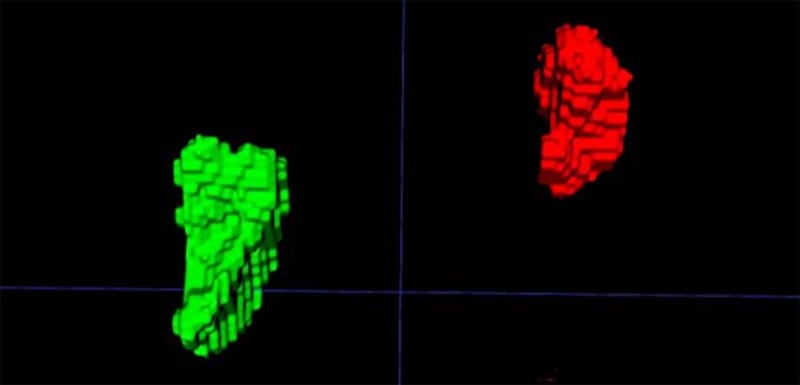

Y es que un equipo de investigadores liderado por la doctora Elena Ghotbi, del Johns Hopkins University School of Medicine, en Estados Unidos, entrenó un modelo de aprendizaje profundo para medir el volumen de las glándulas suprarrenales a partir de tomografías de tórax ya realizadas.

El indicador, llamado Índice de Volumen Suprarrenal (AVI, por sus siglas en inglés), se define como el volumen de las glándulas suprarrenales dividido por la estatura al cuadrado.